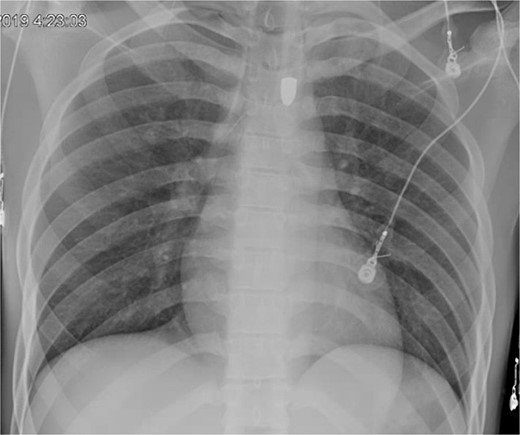

A repeat otolaryngology endoscopy exam on HD 2 revealed a 1.5 cm wound in the posterior pharyngeal wall, confirming the suspicion that the bullet entered the posterior of the mouth, was swallowed, and was now migrating down the GI tract. Serial X-rays tracked its transit (Fig. 4). Despite treatment, his condition remained critical. He underwent tracheostomy, gastrostomy, and diaphragmatic pacemaker placement. The patient was discharged to a long-term care facility on HD 22 but succumbed to complications from AIDS and pneumonia months later.

A FB in the GI tract will pass naturally in most cases. Serial images can be used to monitor transit through the gut. Stools can be monitored for evacuation [4, 5]. Obstruction or perforation by any FB is possible. Concern may be raised if the object fails to progress, especially in the right lower quadrant at the cecum. Patients developing signs of bowel obstruction or peritonitis warrant exploration [12, 13].